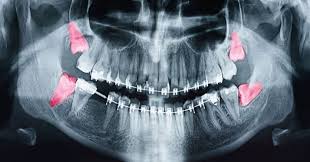

Oral Medicine & Radiology

The Department of Oral Medicine and Dento Maxillofacial Radiology is primarily involved in the diagnosis of all the dental/oral and para oral diseases in a systematic manner and its medical management.

Oral & Maxillofacial Surgery

The Department of Oral & Maxillofacial Surgery established in 1999 with the aim of providing quality care at affordable cost. The Oral & Maxillofacial surgical team works in synchrony with Shree Raghavendra Dental Care Hospital.

Surgical removal of impacted teeth-IMPACTIONSurgical resection of root end attached soft tissues and sealing the root canal-APICOECTOMY